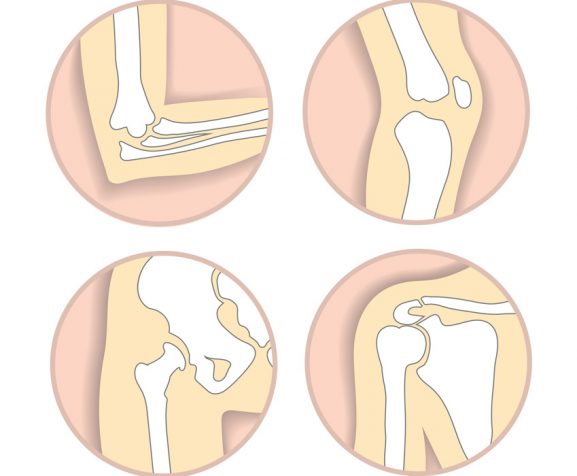

Carpal Tunnel Syndrome

Ligament Tears

Sprains

Stress Injuries

Tendonitis

Tennis & Golfer’s Elbow